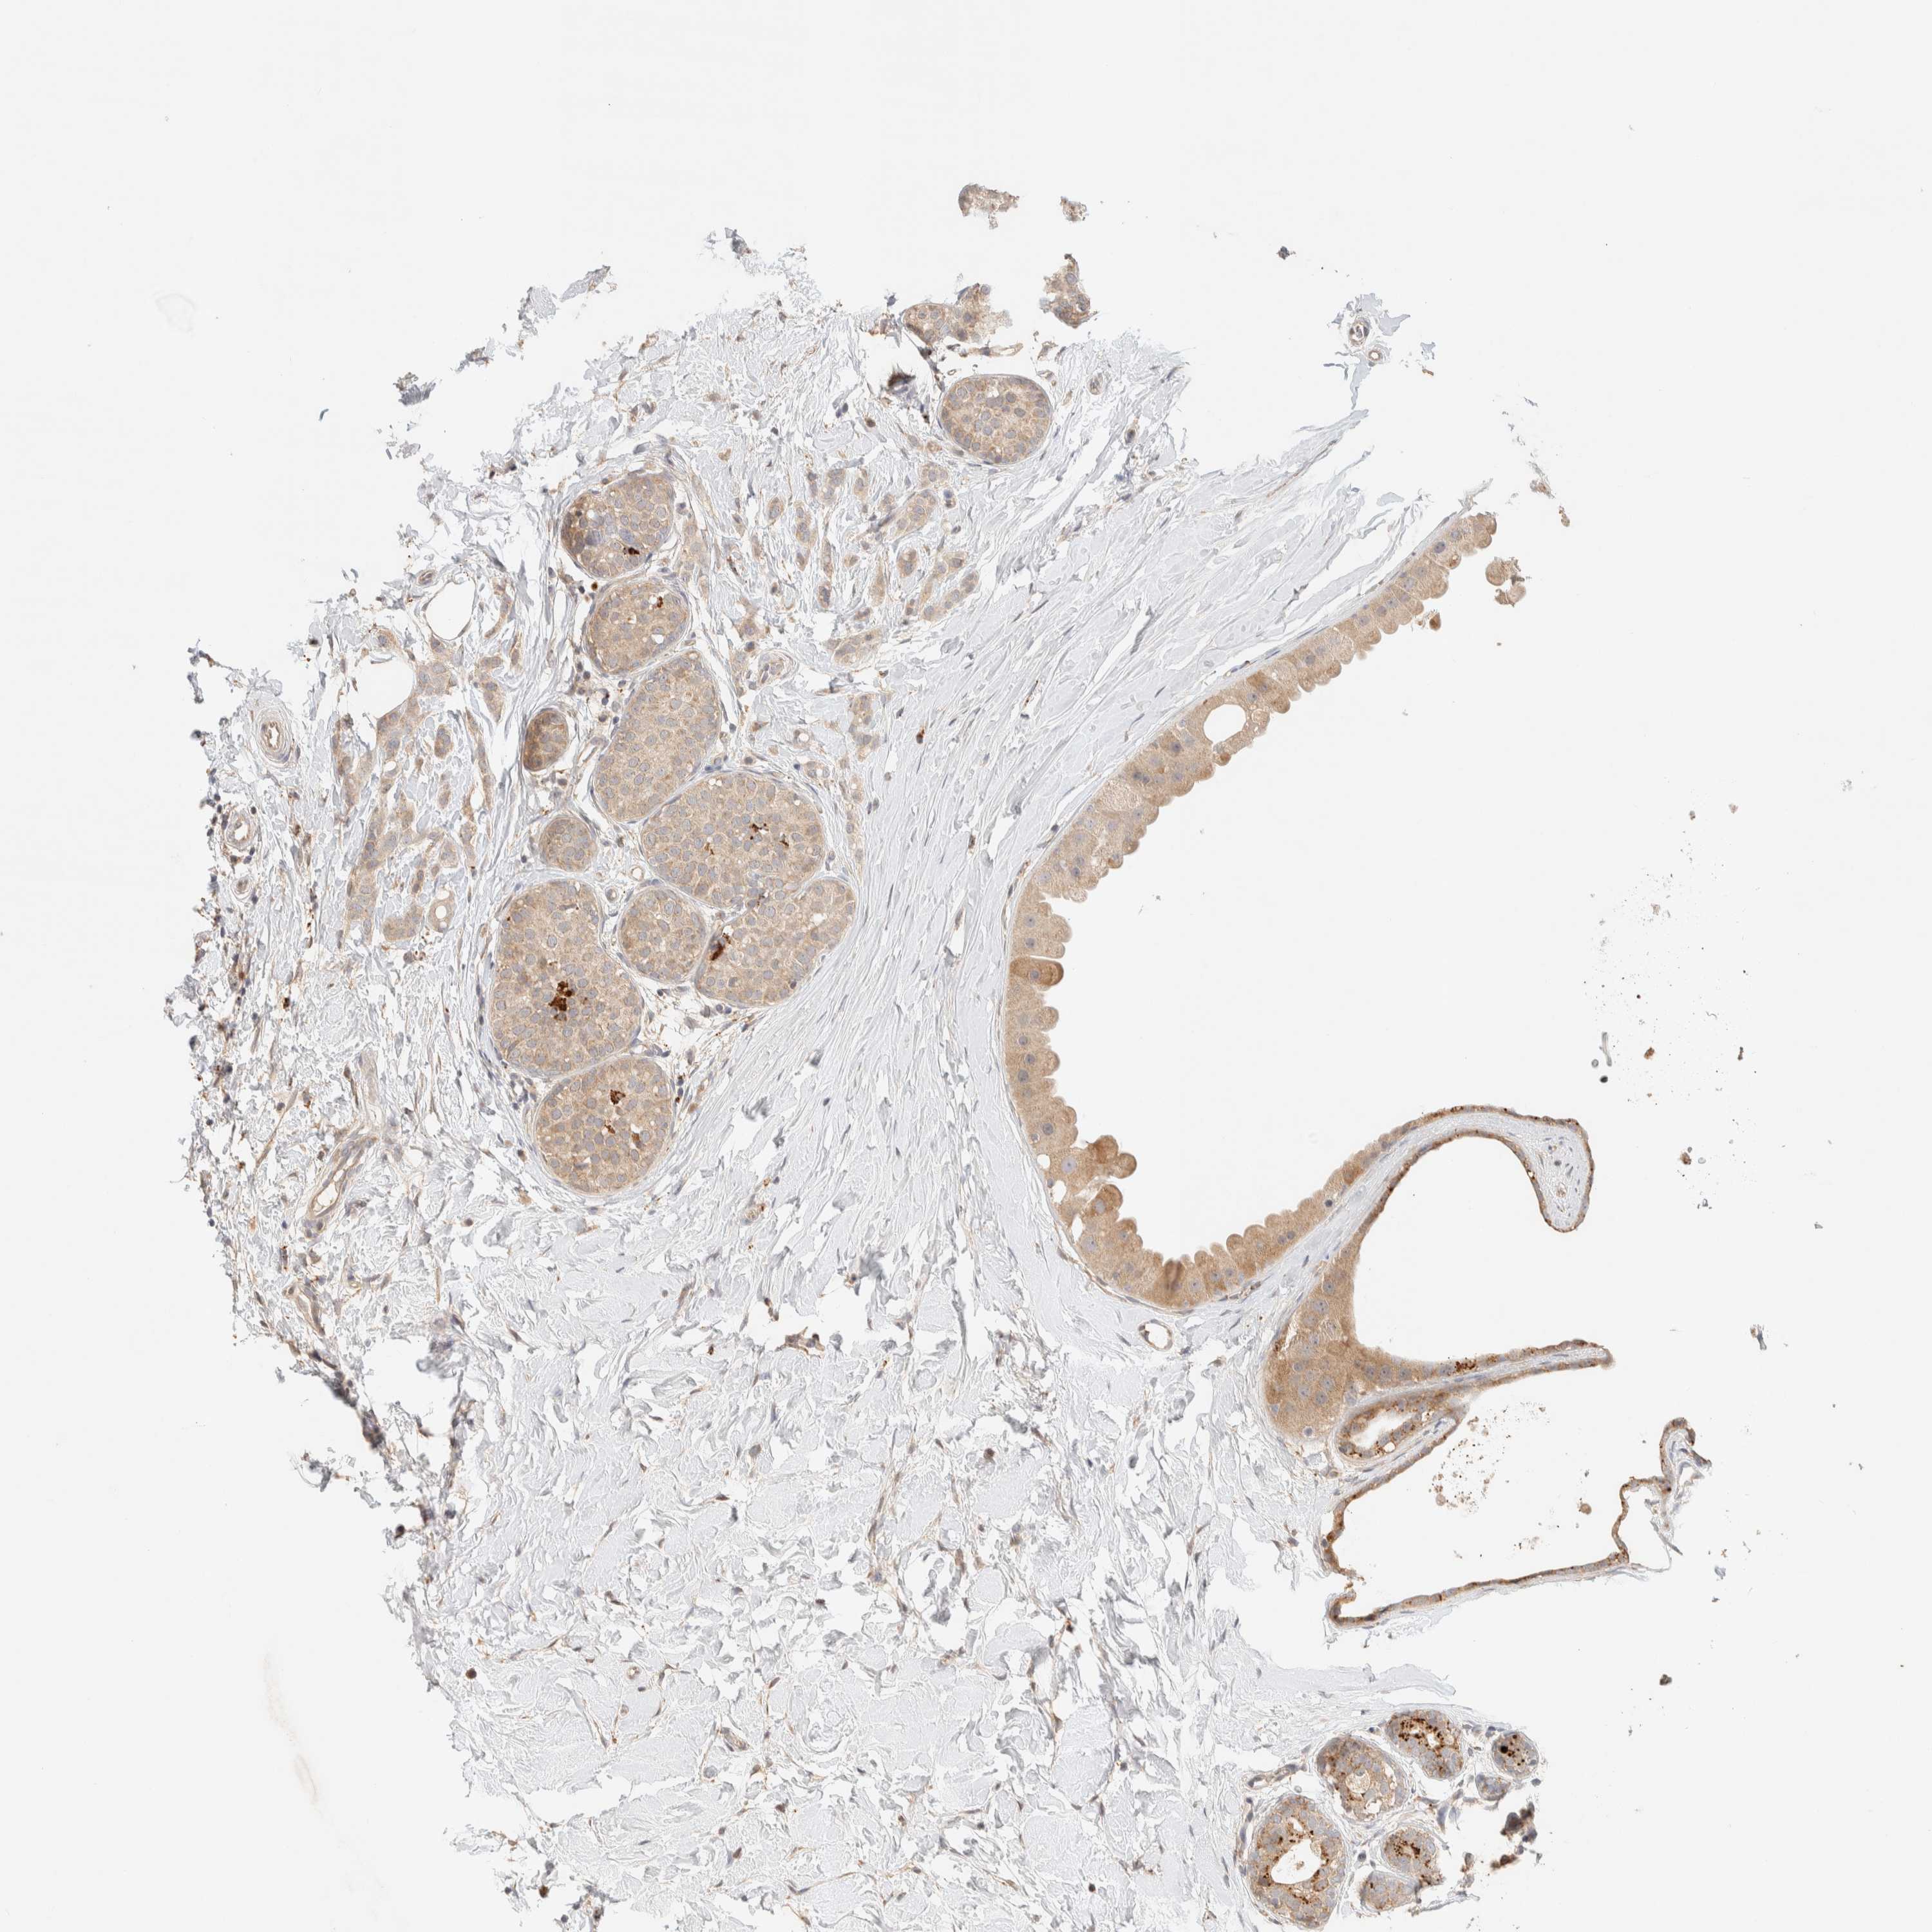

BRCA TCGA BRCA VALIDATION PROTEIN EXPRESSION

ANTIBODIES

AND

VALIDATION